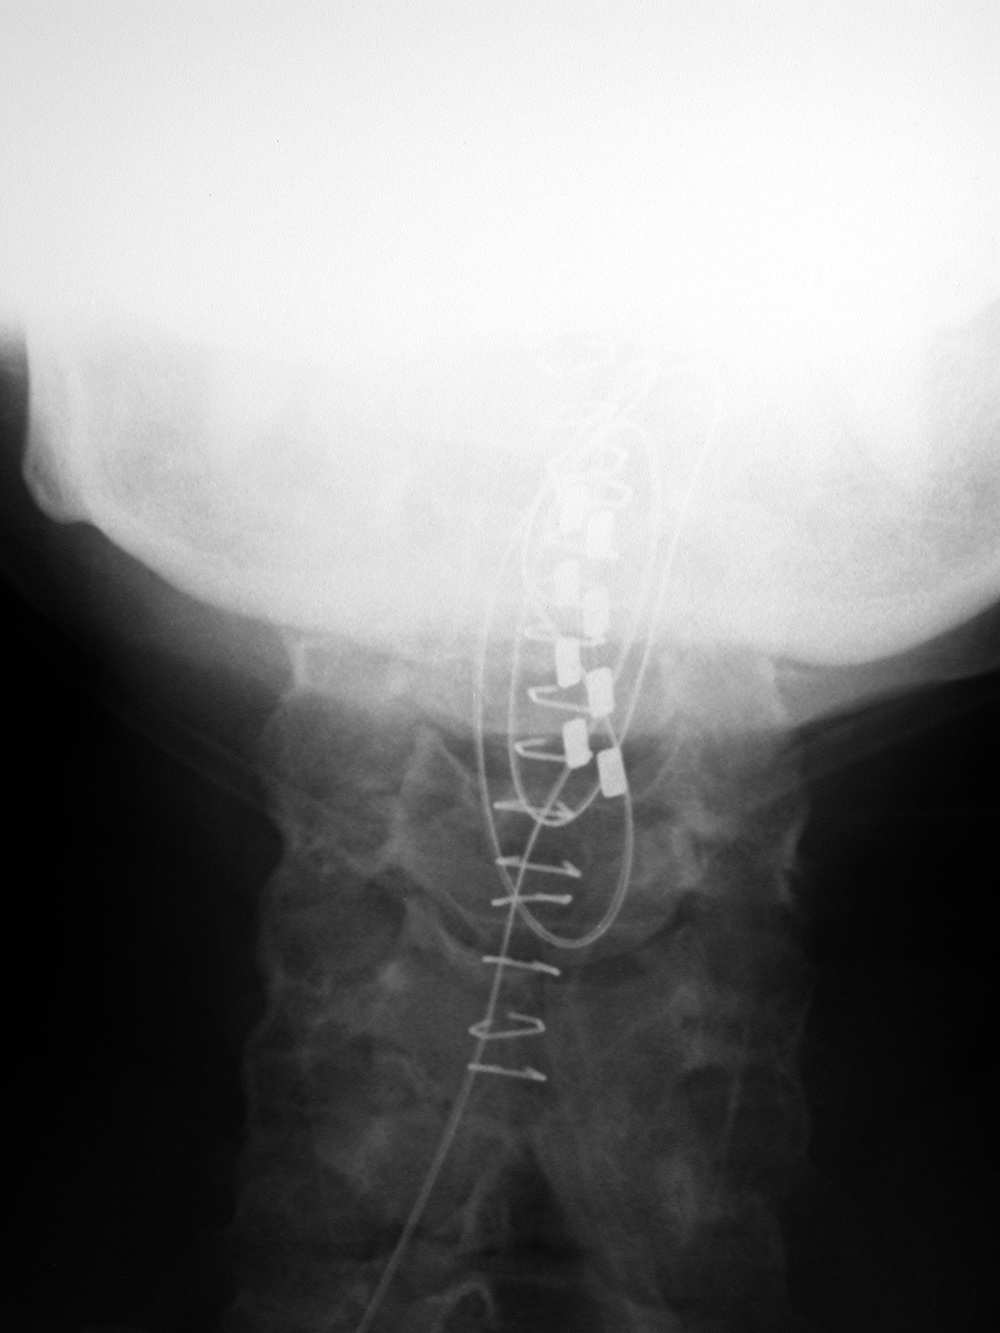

| Dorsal column stimulation unit in upper cervical spine |

Dorsal column stimulation unit in lower thoracic spine |

| There are skin staples from the recent surgery. From Hunter, 2004 |

Congenital fusion of the C5 and C6 vertebral bodies is present. From Hunter, 2004 |